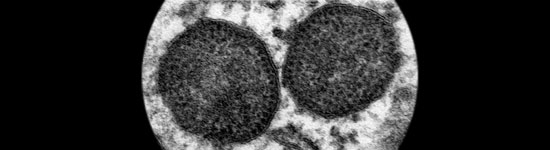

Novedades sobre las vías de excreción, rutas de transmisión, factores de riesgo, etc y la explicación de porqué PCV2 se convierte en un virus patógeno.